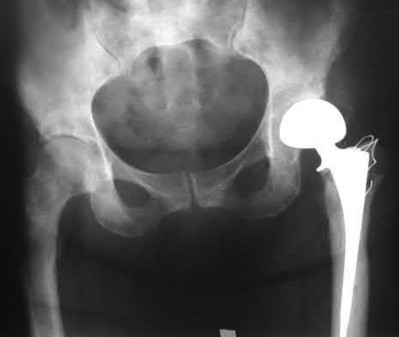

The image shows a reverse obliquity intertrochanteric hip fracture.

According to the referenced article by Haidukewych et al, unstable peritrochanteric hip fractures have a worse outcome (failed in 9/16 cases) if treated with a sliding hip screw. Two additional factors that were found to have a strong correlation with postoperative failure (nonunion, loss of reduction) were poor reduction and poor implant placement. In this study, fixed angle devices were superior. Intramedullary fixation has the added advantage of a shorter lever arm and less potential for fracture collapse and limb shortening.

The IMN also acts as a medial buttress.

According to Sanders et al, the dynamic condylar screw (DCS) can also be used in subtrochanteric models, but should not be used if extensive comminution is seen, as they reported a high failure rate with DCS in these fractures if highly comminuted. They report a 77% overall union rate with this device.